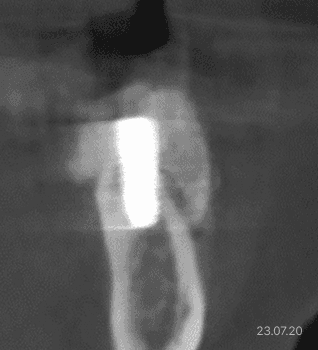

무절개 전용 임플란트 · 절개형 뼈이식 접목

무절개 전용 임플란트 ·

절개형 뼈이식 접목

극심한 잇몸뼈 소실